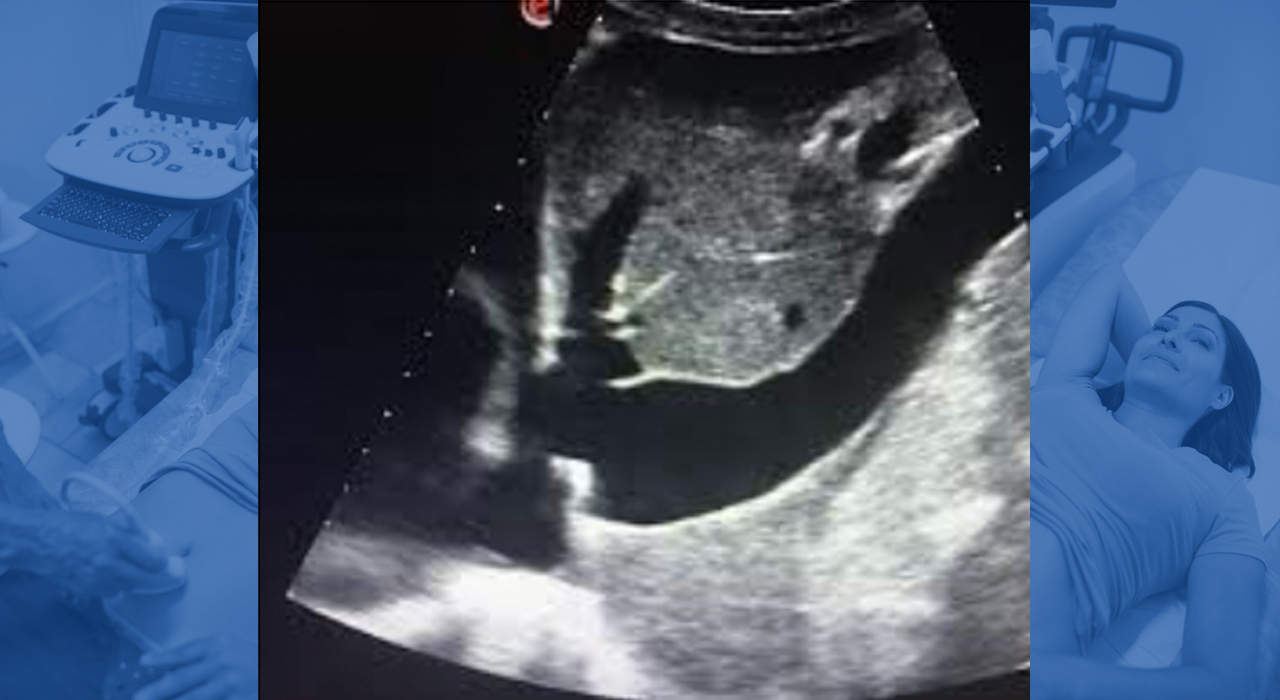

- ÁREAS Y PROTOCOLOS- RCP (Rush), pulmonar, cardiaco, vasos sanguíneos, abdominal, emergencias, trombosis venosa, tejidos blandos y tiroides.